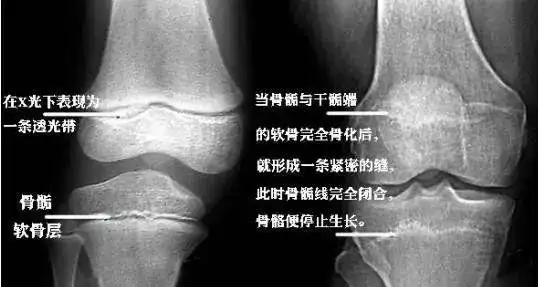

发育科主任蔡西萍一起来了解一下骨骺线是什么,在人的生长发育过程中